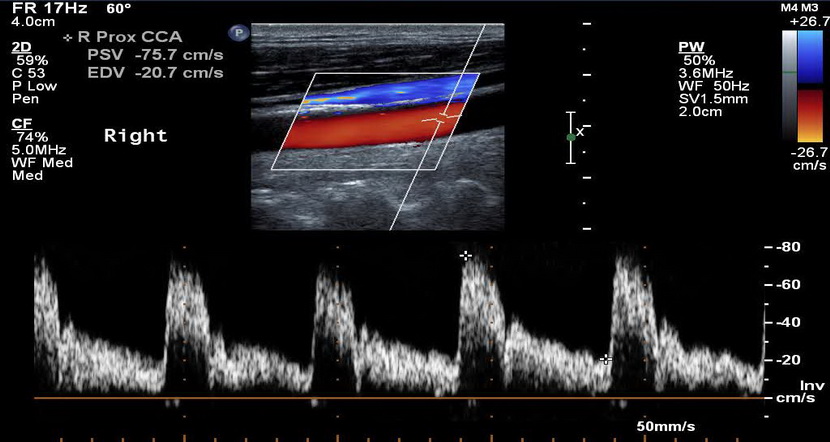

Доплерографія - це сучасний метод ультразвукової діагностики, що широко використовується в медичній практиці для виявлення ураження як артеріальних, так і венозних судин.

За допомогою доплерографії в Івано-Франківську можна повністю обстежити судинне русло голови та шиї, верхніх і нижніх кінцівок, нирок, черевної порожнини, визначити будову судин та їх стінок, візуалізувати наявність аномалій розвитку чи атеросклеротичних бляшок, оцінити гемодинамічні показники кровотоку, ступінь та значимість стенозу артерій, порушення та стан кровоплину в судинах, недостатність функції клапанів у венозних судинах та ін.